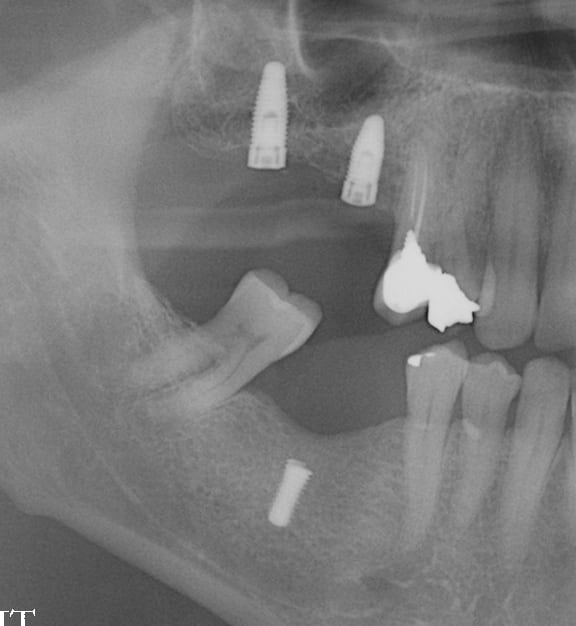

sniff périimplantite

J'ai quelques d'implants avec la même image et je ne touche à rien si l'implant est immobile. Et certains sont là depuis des années...

Une perte osseuse non infectée n'est pas une périimplantite et elle se stabilise à un certain niveau lorsque le système est en bio-équilibre.

Ici, il est dommage que l'implant soit un peu court, ce qui peut entrainer sa perte par surcharge.

Je ne pense pas que ce soit une périimplantite et le tabac n’est pas la cause de la perte osseuse mais un facteur aggravant.